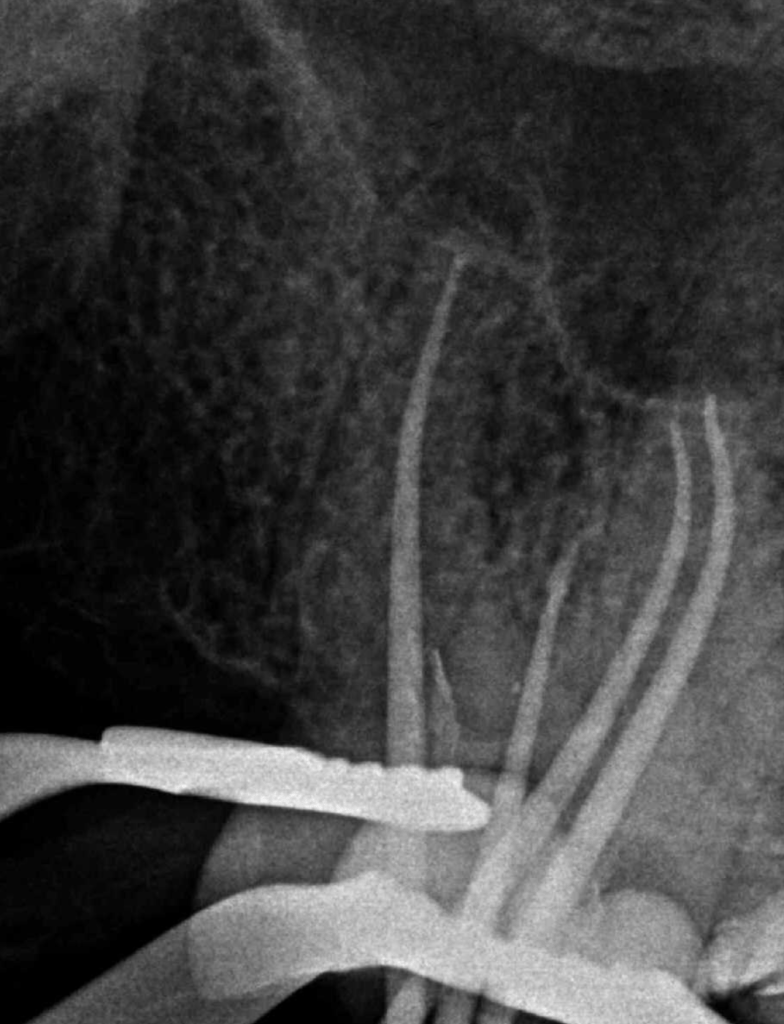

CALCIFICADOS

Premolar calcificado lesion